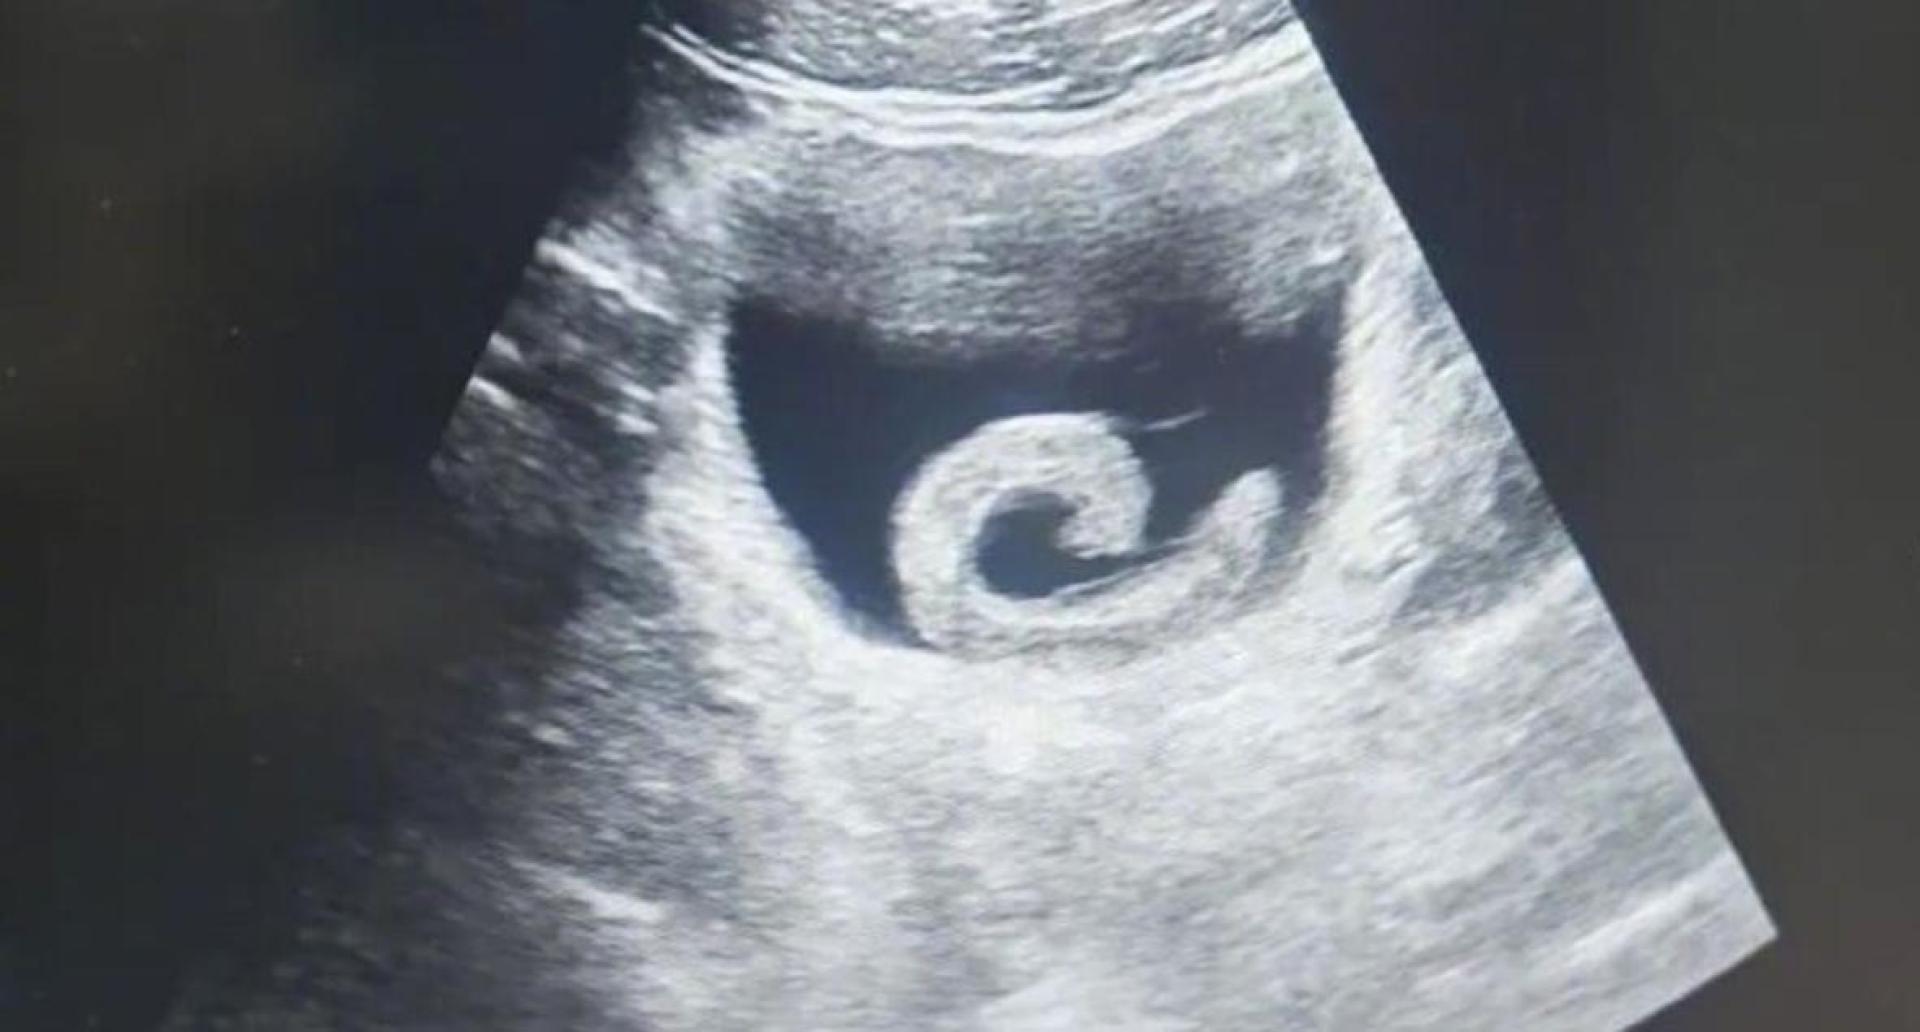

超声波检查下,水蛭被发现在病人膀胱内寄居。

Menurut laporan, lelaki berkenaan tiba di bahagian kecemasan hospital dengan muka pucat dan berpeluh, badannya membongkok dan kedua-dua tangan menahan bahagian bawah perut. Wajahnya berkerut kerana menanggung kesakitan teramat serta ketakutan. Doktor segera melakukan pemeriksaan ultrabunyi dan mendapati terdapat objek berbentuk seperti jalur yang sedang bergerak di dalam pundi kencing lelaki itu, dengan tanda-tanda pendarahan di sekitarnya.

Timbalan Ketua Pakar Urologi melakukan pemeriksaan endoskopi dan ternampak seekor lintah sepanjang kira-kira 5 hingga 6 sentimeter di dalam pundi kencing, melekat pada lapisan mukosa pundi kencing yang mengalami pembengkakan dan pendarahan serius. Inilah punca lelaki itu mengalami kesakitan melampau dan tidak dapat membuang air kecil.